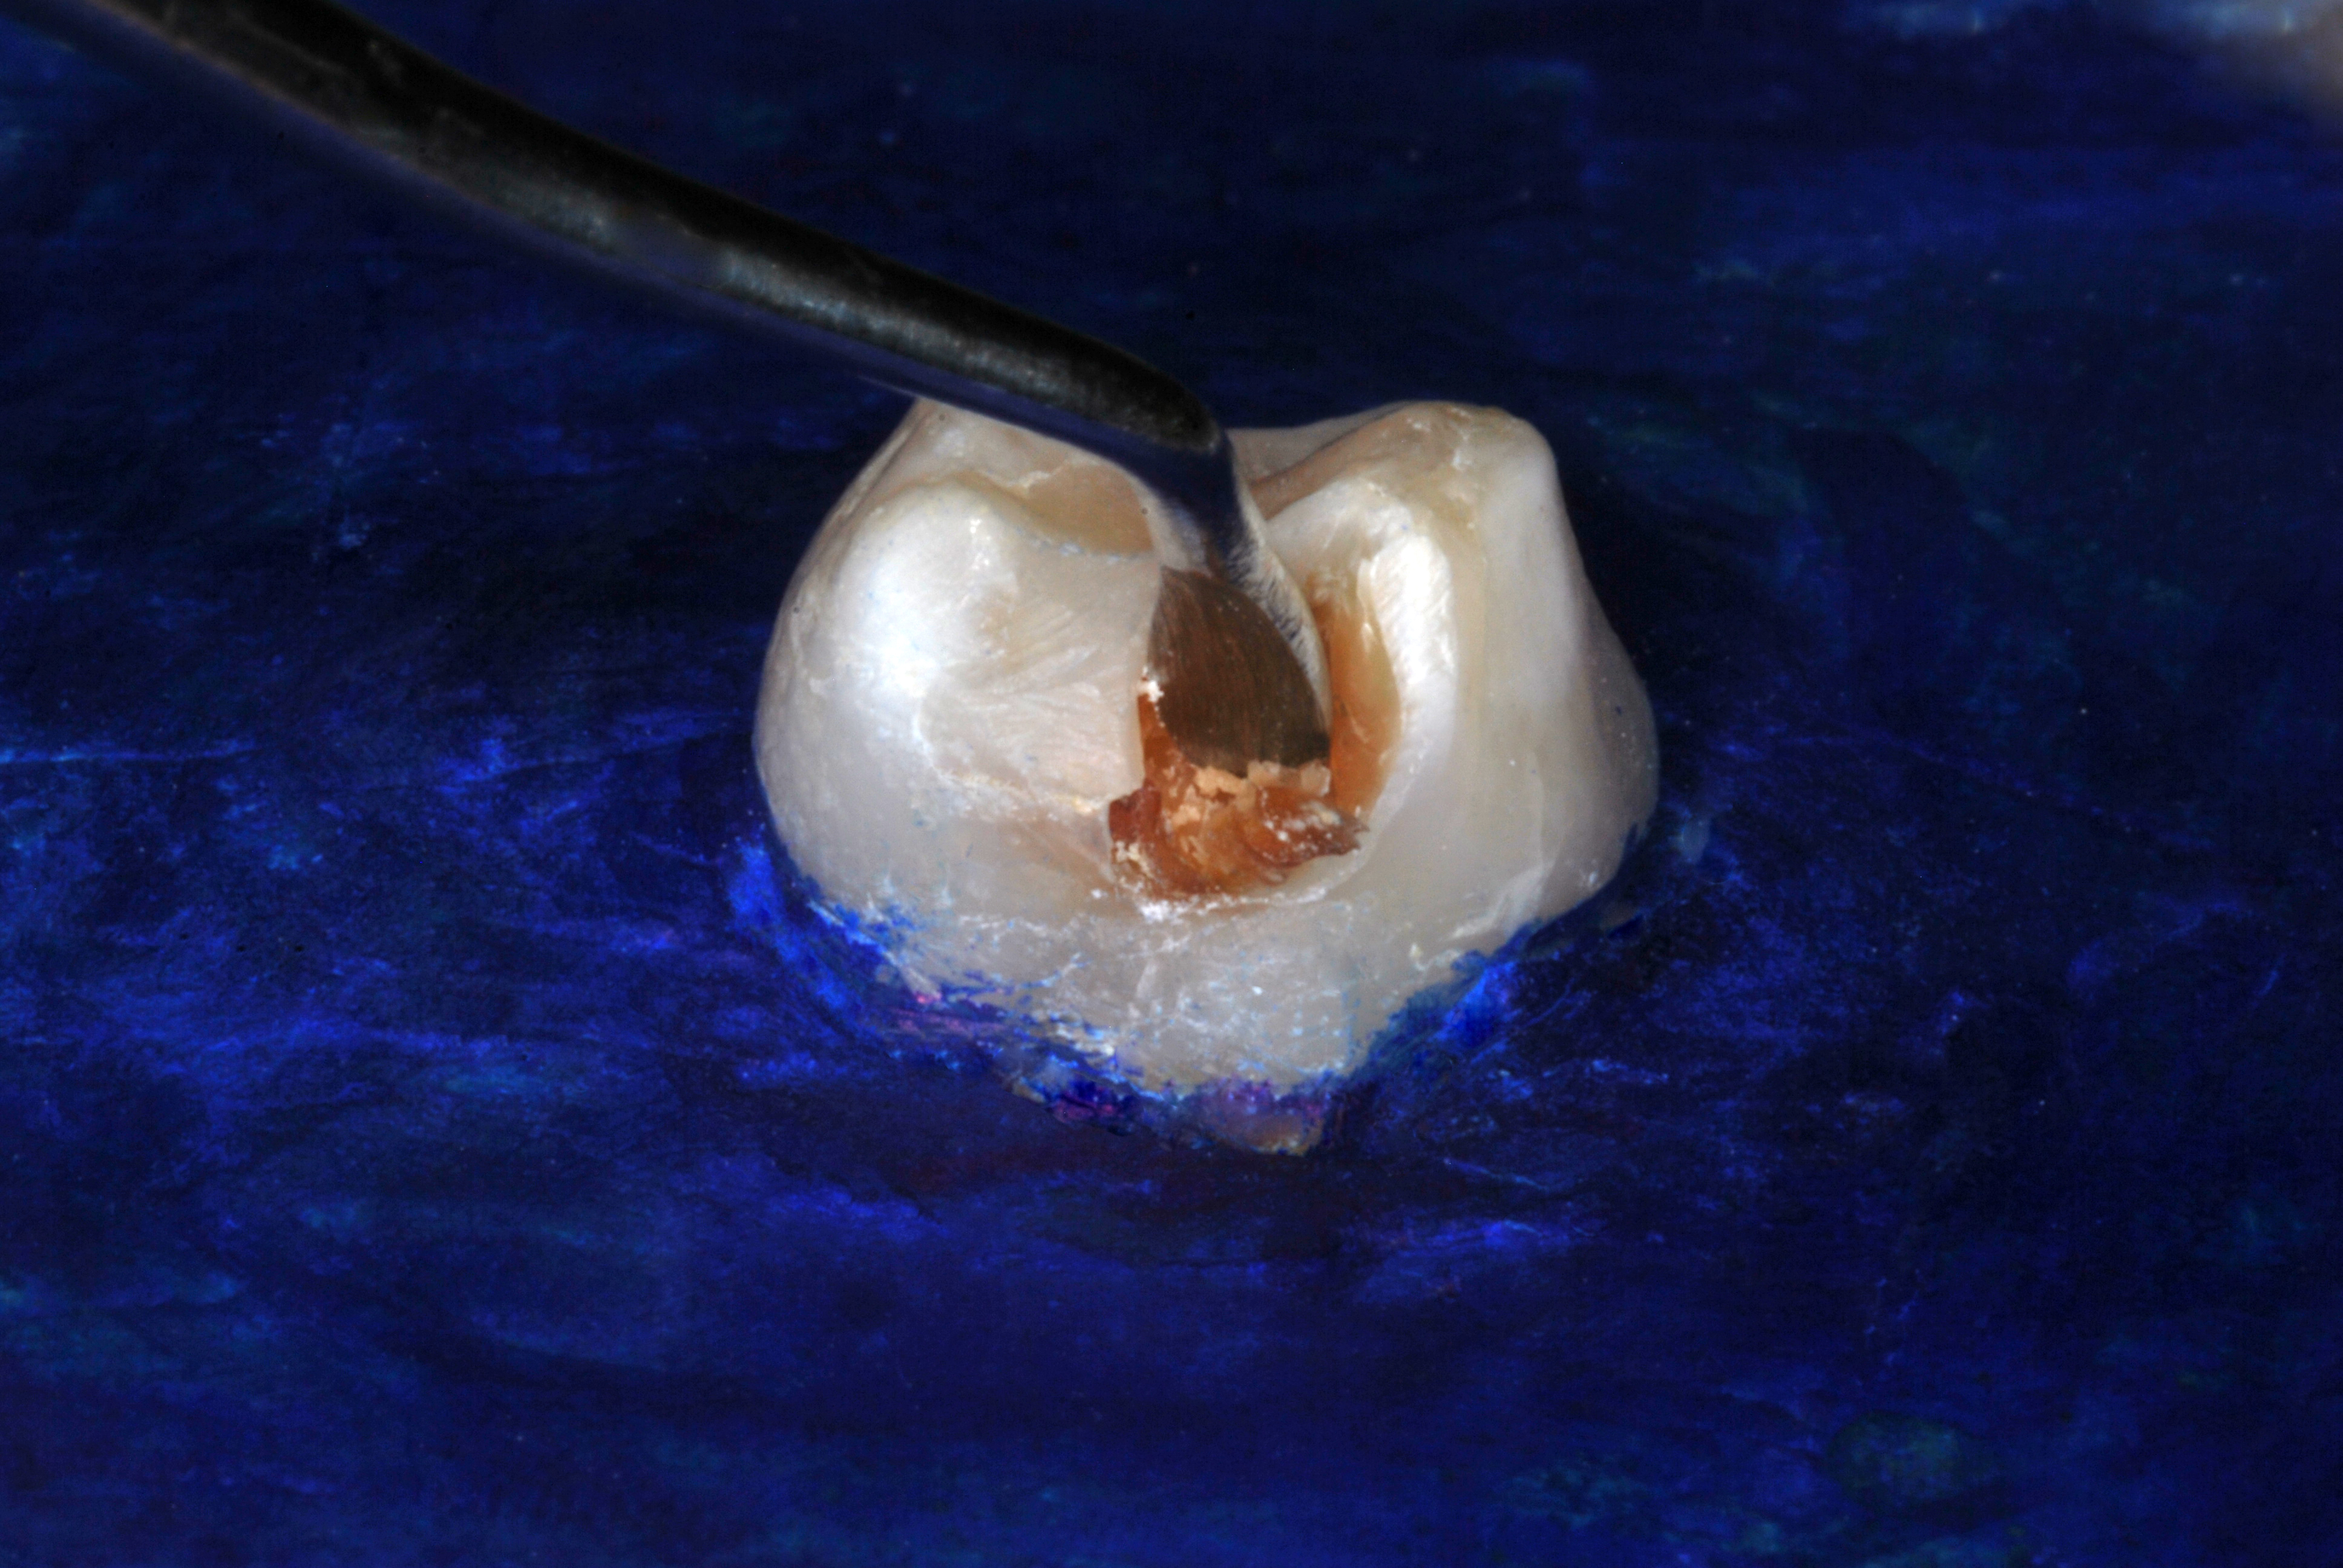

(26.) Silver modified atraumatic restorative technique (SMART) caries control treatment demonstrated on extracted carious primary molar.

Figure 26